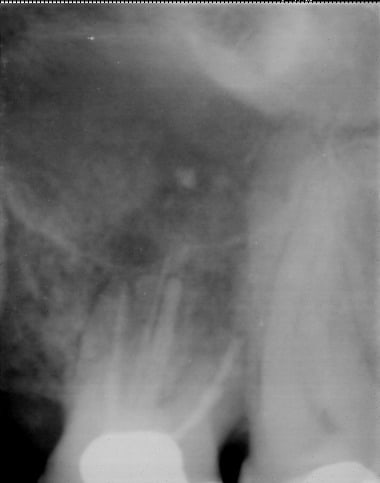

Aprés les débats sur la digue et les implants, comme la patate est chaude, voici le cas de cette 26, chez un patient de 55 ans, reprise de traitement, avec aussi incroyable que ça puisse paraitre un arret net à la progression de la lime et obtu à cette butée. Radio 6 mois aprés.

Résorption généralisée au niveau radiculaire, pas d'autres radios sous le coude, y'a une perte osseuse en mésial, avec un léger regain, la dent est légérement mobile, mais sans douleur pour le patient.

c'est bien mais le but c'est quoi narik? Tu as une fonte paro importante des deux cotés. Ok ton TR est un succes a court terme et peut etre a long terme mais vu la quantité d'os qui te reste, penses tu attendre l'atteinte de furcation, ou tu preferes que la racine distale flotte dans le vide? Comment ce patient fait il pour brosser sa poche paro qui si la radio n'est pas trop defilée lui laisse 3 à 4 mm d'os autour de son apex?

bémol : ta radio est défilée mais je ne sais pas de combien donc c'est quand meme trompeur mais dans le cas ou elle ne l'est pas trop, moi je conserve pas désolé.

Question subsidiaire : la racine de la dent mésiale 24 ou 25, il lui reste combien de temps a vivre vu la fente paro, le liseret foncé qui sert de ligament parodontal? Cf radio "AVANT"